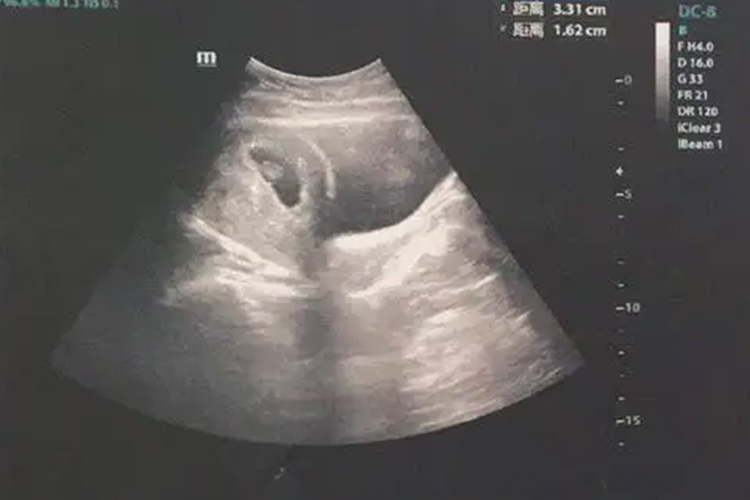

妊娠6周时,B超可见到胚芽和原始心管搏动。

怀孕早期B超检查的主要目的是确定宫内妊娠,排除异位妊娠、滋养细胞疾病、盆腔肿块等。若为多胎,可通过胚囊数目和形态判断绒毛膜性。停经35日时,宫腔内见到圆形或椭圆形妊娠囊;妊娠6周时,可见到胚芽和原始心管搏动,妊娠11-13周测量胎儿头臀长度能较准确地估计孕周,校正预产期。